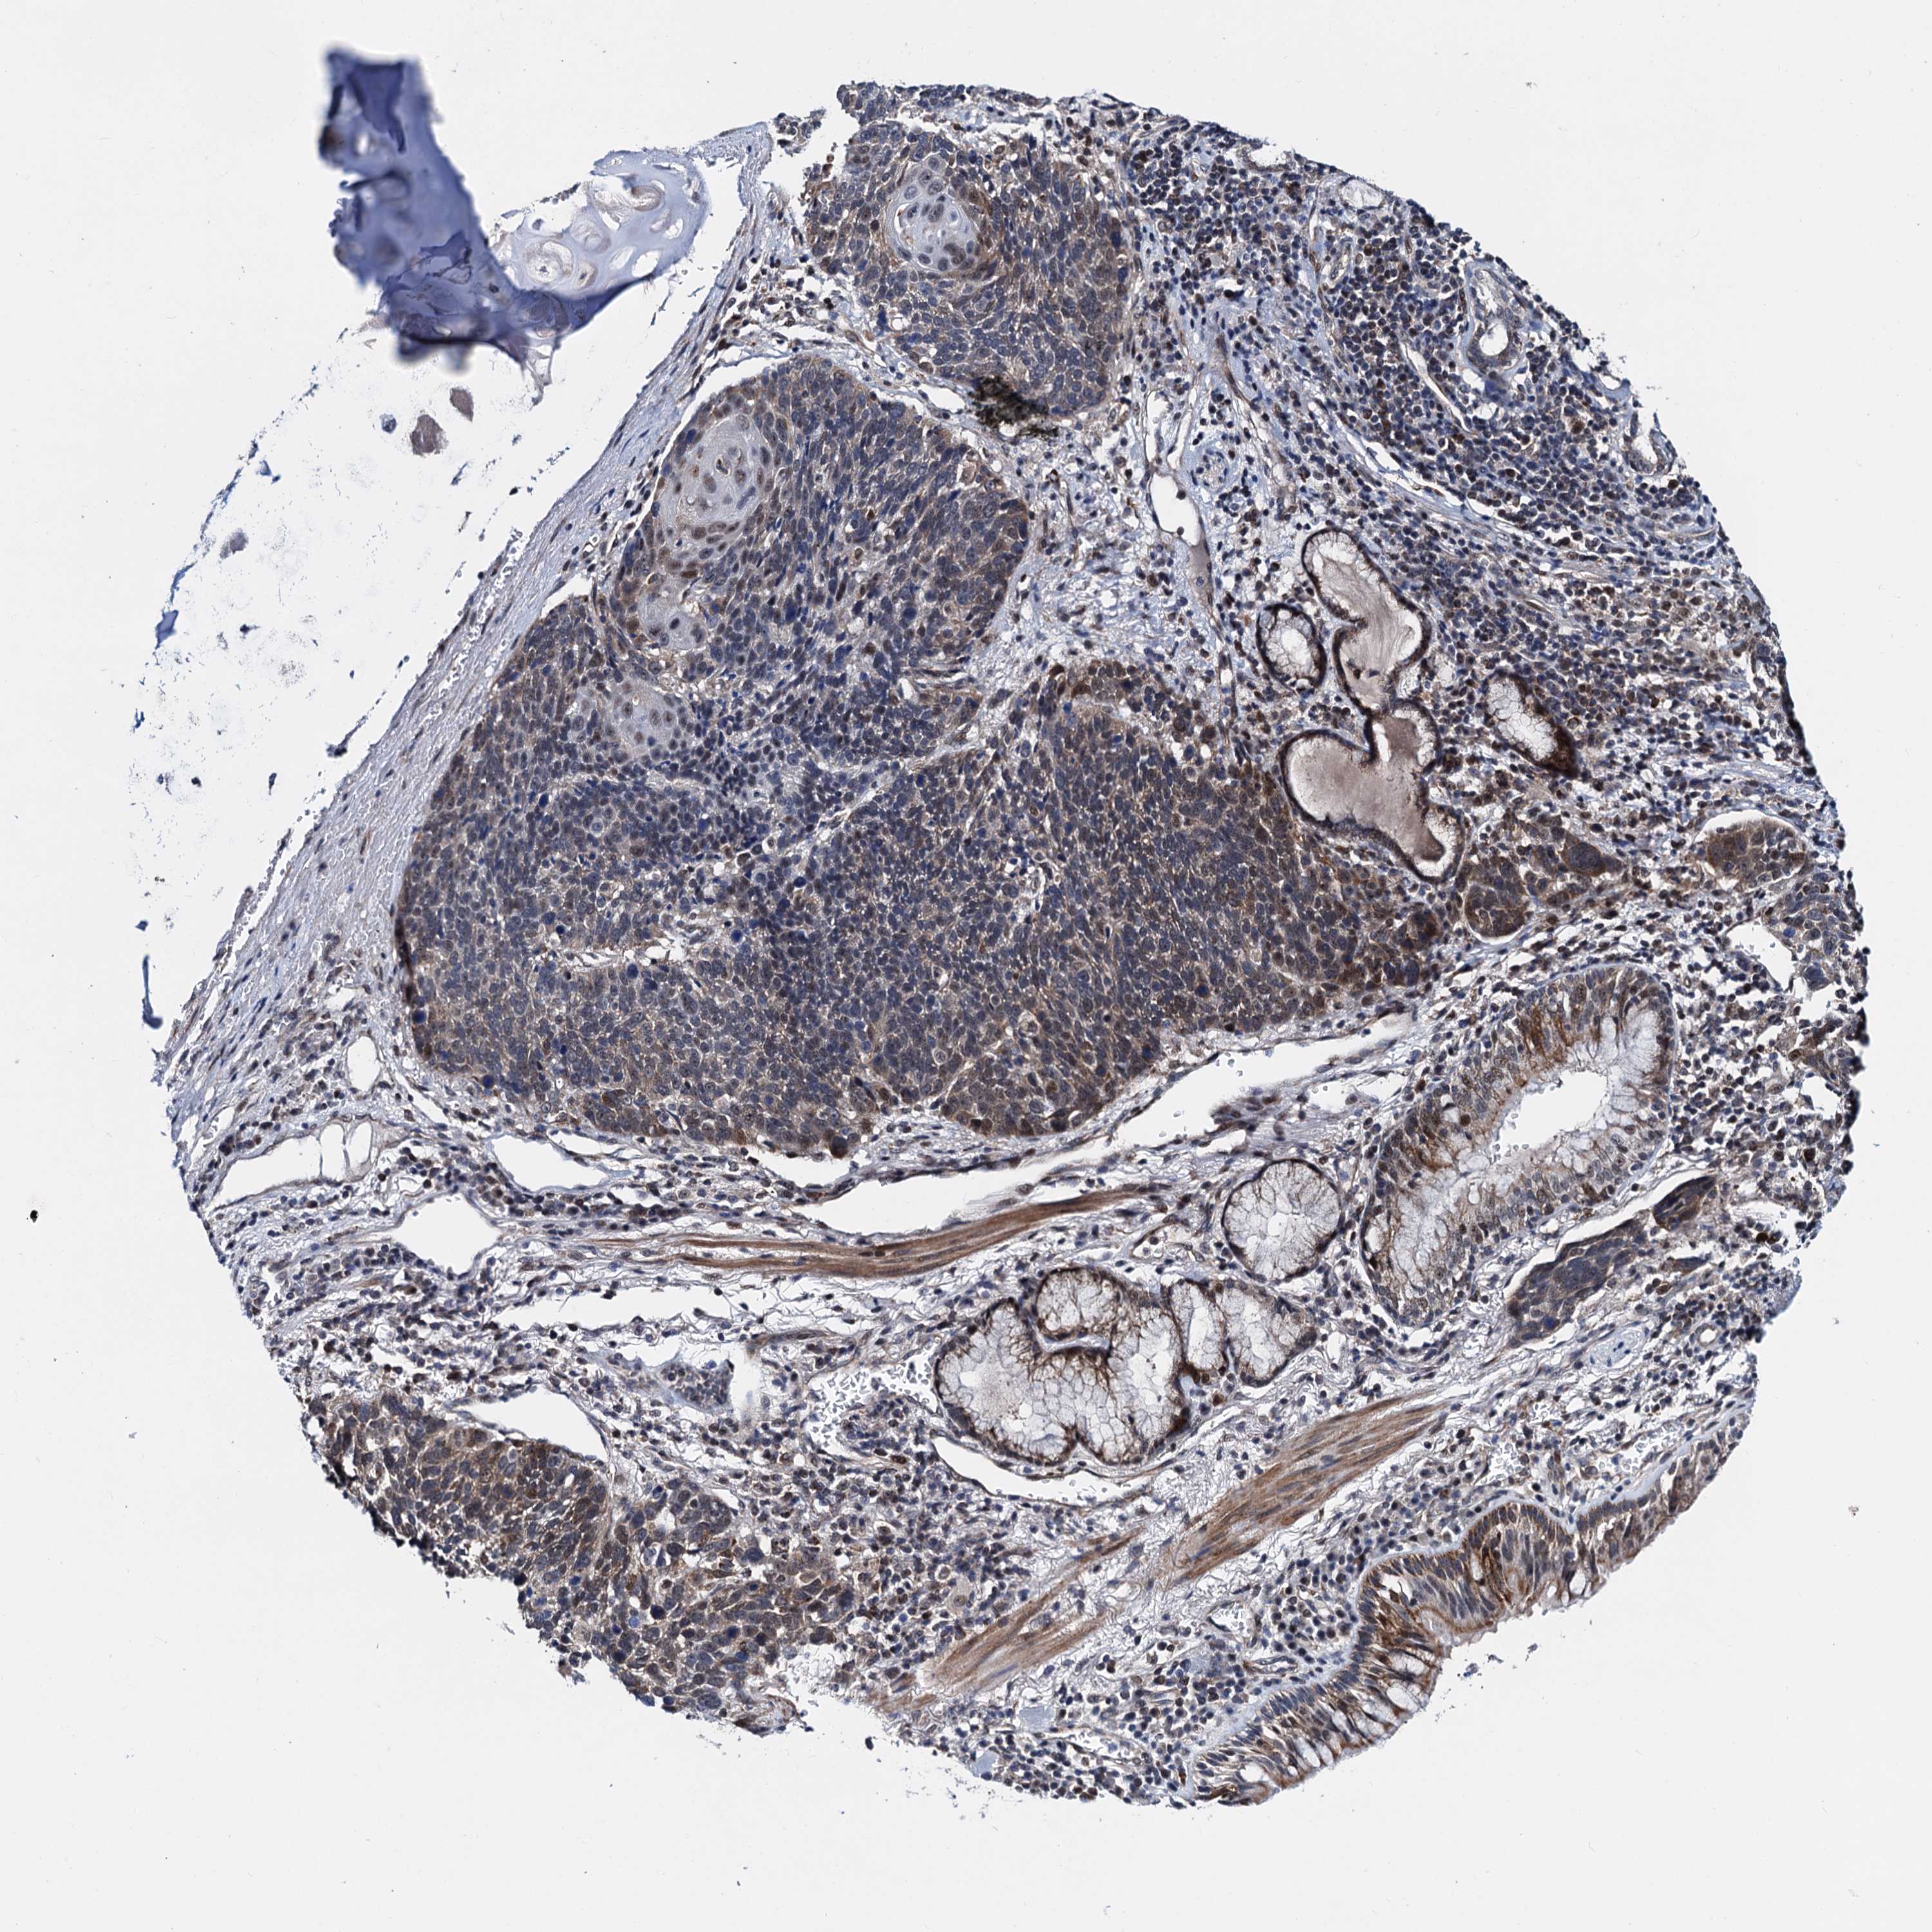

CANCER LUNG CANCER Show tissue menu

LUAD TCGA LUAD VALIDATION LUSC TCGA LUSC VALIDATION PROTEIN LUAD CPTAC PROTEIN LUSC CPTAC PROTEIN EXPRESSION